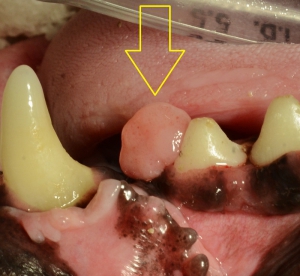

まず、エプリスとは何かという説明として下の2枚の写真をご覧ください。写真は上顎の犬歯のすぐ後ろから発生した良性の骨性エプリス(骨形成性エプリス)ですが、前後の隣接する歯まで覆い隠すほどの大きさです。(右が拡大です)